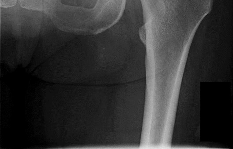

Question 1

A 12-year-old obese boy presents with vague left thigh and knee pain. He is diagnosed with a Slipped Capital Femoral Epiphysis (SCFE) as seen in similar clinical scenarios.

During percutaneous in-situ fixation, unrecognized penetration of the guide wire into the hip joint occurs. What is the most likely specific complication resulting from this technical error?

Explanation

Chondrolysis is a severe complication of SCFE characterized by rapid destruction of the articular cartilage. While it can occur idiopathically, its most established iatrogenic cause is unrecognized intra-articular hardware penetration. The 'approach-withdraw' fluoroscopic technique is required during pinning to assure pins are entirely intraosseous. Avascular necrosis (AVN) is usually due to damage to the epiphyseal blood supply (retinacular vessels) secondary to the initial displacement, forceful closed reduction, or posterosuperior pin placement.